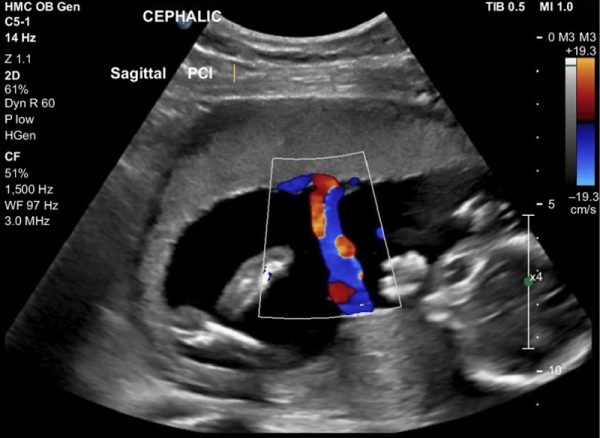

Máy siêu âm Doppler màu, máy siêu âm 4D Voluson P8… cho các thông số chính xác về sức khỏe mẹ và bé